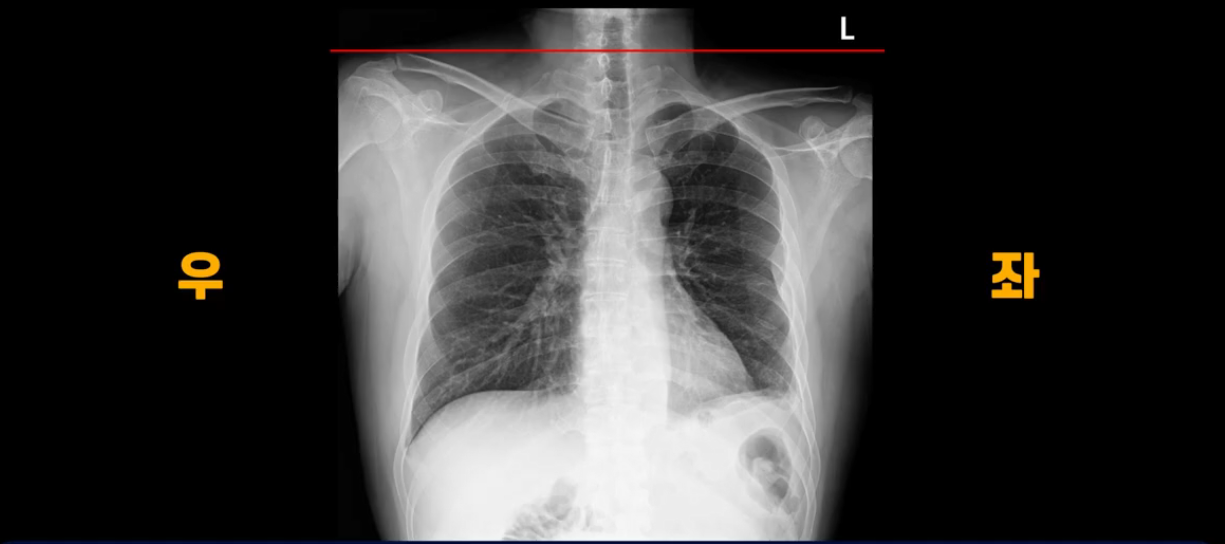

이분 X-ray 사진을 보시죠. 쇄골을 보면 어깨높이가 좌우가 완전히 달라져 있습니다.

몸이 완전히 틀어져 버린 겁니다. 이렇게 몸이 뒤틀리니까 보존 치료 10개월 후에는 한쪽 팔이 저리는 목디스크 증상까지 생기게 됩니다.

본인은 10개월간 보존 치료 열심히 잘했다고 생각했는데 결국은 다리 방사통은 더 심해지고 없던 목디스크 증상까지 생겼습니다. 허리와 골반 근육들이 경직되고 굳어버리면서 몸이 틀어지니까 보존 치료 백날 해봤자 좋아지질 않는데 신경이 눌려 있다는 데만 생각이 꽂혀있어서 최후의 수단으로 수술 받을 생각만 합니다. 이렇게 근육이 심하게 경직되고 굳어버리고 뒤틀리면 디스크에 가해지는 압력이 증가되어 수술 후에도 재파열 가능성이 높아집니다. 여러분이 주위에 척추 수술 후도 지속적으로 허리가 뻐근하면서 상태가 안 좋은 분들 보신다면 그건 바로 수술의 문제가 아니라 허리 근육 기능들이 전부 다 망가져 있기 때문에 신경을 풀어놔도 안 좋은 겁니다.